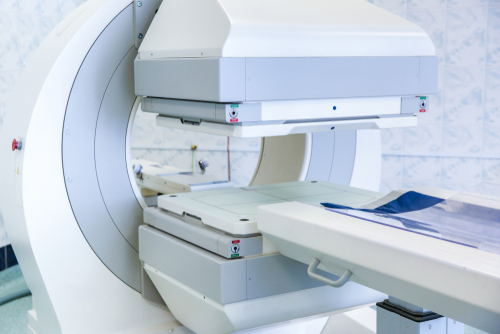

Diagnostic nuclear medicine involves the use of radioactive tracers to image and/or measure the global or regional function of an organ. The radioactive tracer (radiopharmaceutical) is given to the patient by intravenous injection, orally or by other routes depending on the organ and the function to be studied. The uptake, turnover and/or excretion of the tracer substance is then studied with a gamma camera, positron emission tomography (PET) camera or another instrument, such as a simple stationary radiation detector. The uptake of the tracer is generally a measure of the organ function or metabolism or the organ blood flow. ©IAEA